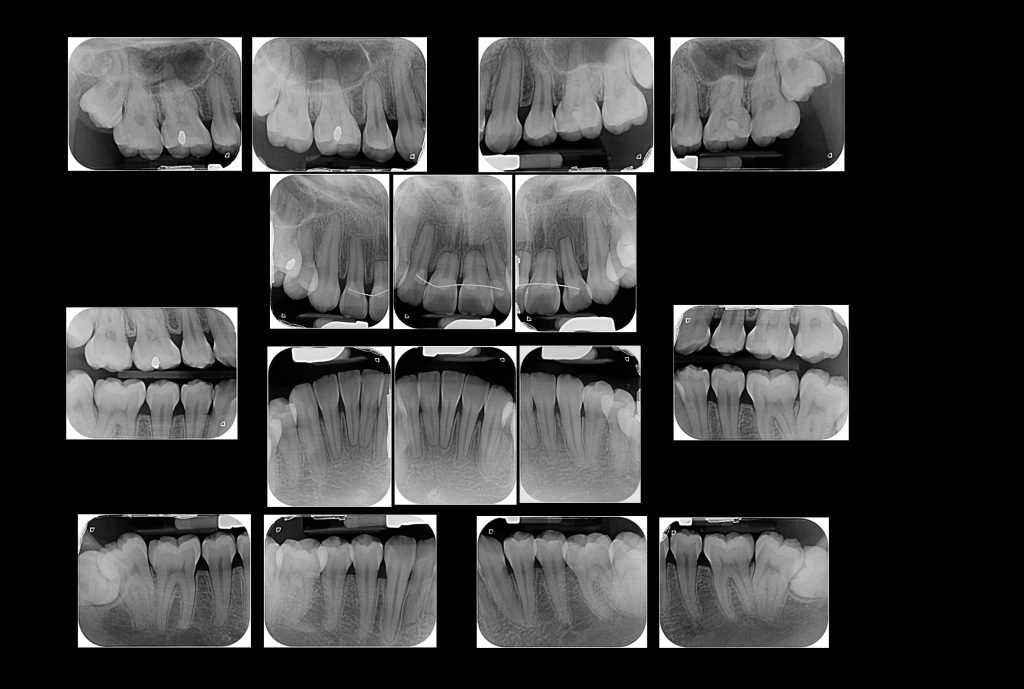

El Centro Radiológico Diagnóstico Oral 3D, es una empresa antioqueña que ofrece a sus pacientes desde el año 2009, tecnología de vanguardia en radiografías tridimensionales con calidad fotográfica. Las posibilidades para mejorar la eficacia en los diagnósticos bucales son evidentes, también lo son las posibilidades de manipulación de imagen. El sistema de imágenes en 3D ofrece detalles sin precedentes, convirtiéndola en la opción idónea para la mayoría de aplicaciones odontológicas, incluyendo implantes, tratamiento de conductos, ortodoncia, odontopediatría, periodoncia y cirugía

El mayor beneficiado con el uso de esta tecnología es el paciente, el cual podrá ser evaluado en todas sus dimensiones con una baja dosis de radiación, con un costo accesible y sin contaminar  el medio ambiente. Dependiendo de la necesidad del paciente, hay varios tipos de tomografías y los especialistas en el área odontológica hacen uso de ellas según su especialidad.

La radiología oral especializada es fundamental para una práctica dental integral, proporcionando información específica que influye en la toma de decisiones clínicas y mejora los resultados del tratamiento para los pacientes

Diagnóstico de caries y enfermedades periodontales

Evaluación de patologías dentales y maxilofaciales

Planificación de tratamientos ortodónticos y ortognáticos

Implantología dental

Diagnóstico de traumatismos dentales y maxilofaciales

Detección de lesiones quísticas y tumorales

Evaluación pre y postoperatoria de cirugías maxilofaciales